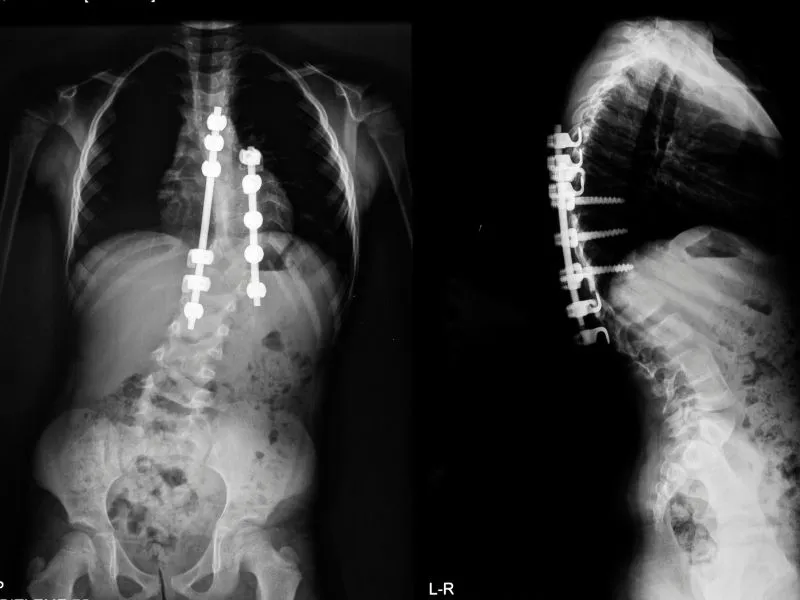

Tratamento cirúrgico da escoliose idiopática

A cirurgia é indicada em casos mais graves, quando a curvatura ultrapassa os 50 graus ou compromete funções respiratórias, causa dor intensa ou afeta significativamente a estética corporal. O procedimento utiliza hastes e parafusos para corrigir e estabilizar a coluna.

De acordo com o estudo, pacientes operados apresentam melhor correção radiográfica da curva e resultados mais estáveis ao longo de 10 anos. Apesar de alguma perda parcial da correção com o tempo, os resultados permanecem duradouros e a qualidade de vida é comparável à dos pacientes tratados de forma conservadora.